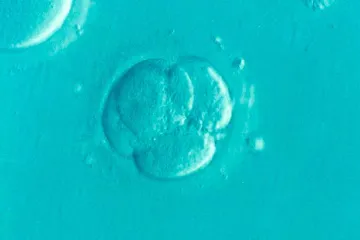

A Suprema Corte do Alabama decidiu na última sexta-feira (16) que embriões humanos congelados são crianças segundo lei do Estado, uma decisão que poderá ter efeitos de grande alcance em fertilizações in vitro e outras questões médicas no país.

A decisão da Suprema Corte de Alabama é para uma ação judicial movida por vários pais cujos embriões congelados foram acidentalmente destruídos numa clínica de fertilidade. Os requerentes argumentaram que a destruição se enquadrava na Lei de Morte Injusta de Menor do Alabama.